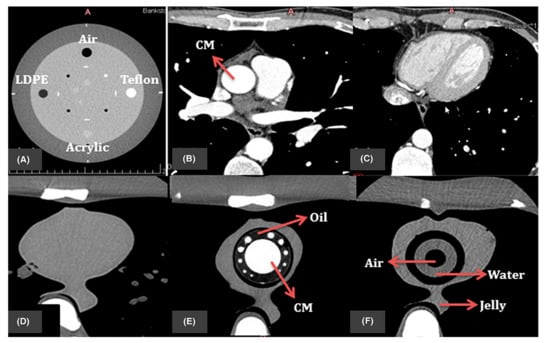

- Sun, Z.; Ng, C.K.C.; Wong, Y.H.; Yeong, C.H. 3D-Printed Coronary Plaques to Simulate High Calcification in the Coronary Arteries for Investigation of Blooming Artifacts. Biomolecules 2021, 11, 1307. [Google Scholar] [CrossRef]

- Sun, Z.; Ng, C.K.C.; Squelch, A. Synchrotron radiation computed tomography assessment of calcified plaques and coronary stenosis with different slice thicknesses and beam energies on 3D printed coronary models. Quant. Imaging Med. Surg. 2019, 9, 6–22. [Google Scholar] [CrossRef] [PubMed]

- Sun, Z. 3D printed coronary models offer new opportunities for developing optimal coronary CT angiography protocols in imaging coronary stents. Quant. Imaging Med. Surg. 2019, 9, 1350–1355. [Google Scholar] [CrossRef]

- Sun, Z.; Jansen, S. Personalized 3D printed coronary models in coronary stenting. Quant. Imaging Med. Surg. 2019, 9, 1356–1367. [Google Scholar] [CrossRef]

- Abdullah, K.A.; McEntee, M.F.; Reed, W.; Kench, P.L. Development of an organ-specific insert phantom generated using a 3D printer for investigations of cardiac computed tomography protocols. J. Med. Radiat. Sci. 2018, 65, 175–183. [Google Scholar] [CrossRef]

- Mørup, S.D.; Stowe, J.; Precht, H.; Gervig, M.H.; Foley, S. Design of a 3D printed coronary artery model for CT optimization. Radiography 2022, 28, 426–432. [Google Scholar] [CrossRef]